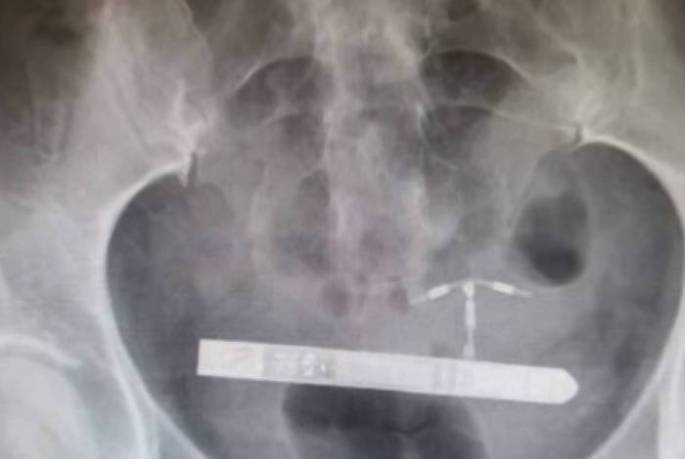

Após vibrador parar na bexiga, mulher precisa ser operada

Ela relatou que toda vez que o objeto vibrava 'era como se todo o seu abdômen se mexesse' A mulher estava em uma brincadeira sexual com seu parceiro quando aconteceu o acidente. O objeto de 9 cm entrou no corpo dela e a norte-americana precisou passar por uma cirurgia para tirar o vibrador do corpo. … Continue lendo Após vibrador parar na bexiga, mulher precisa ser operada